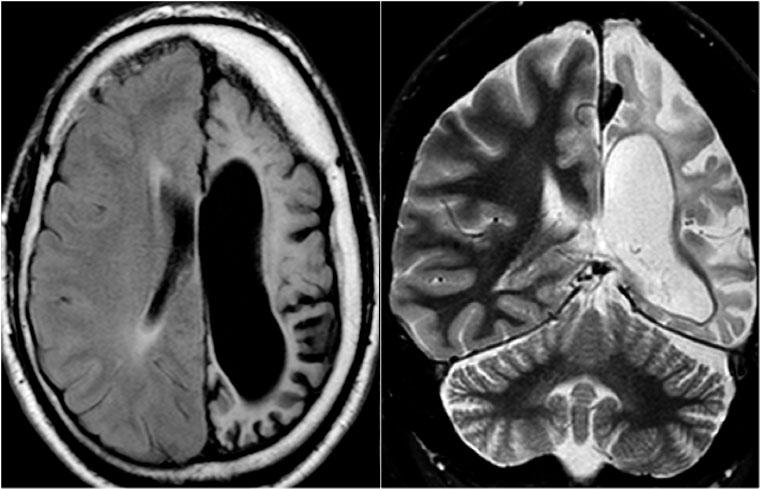

Hemimegalencephaly bên trái với loạn sản vỏ não lan tỏa vùng trán-đỉnh (mũi tên xanh) và tăng tín hiệu T2W lan tỏa chất trắng

Hình ảnh CT và chuỗi xung T2W trên bệnh nhân hemimegalencephaly bên phải.

Ghi nhận vỏ não dày loạn sản và giãn não thất ở bên bị tổn thương.

Bé gái 9 tuổi với động kinh về đêm kháng trị.

MRI cho thấy hình ảnh phì đại bán cầu đại não trái.

Chuỗi xung T1W ghi nhận chất xám lạc chỗ (heterotopic gray matter) lót dọc theo thành não thất bên trái (mũi tên xanh).

Trong hemimegalencephaly, điều quan trọng là cần loại trừ các bất thường ở bán cầu đối bên, vì đây là chống chỉ định của phẫu thuật cắt bán cầu não (hemispherectomy).